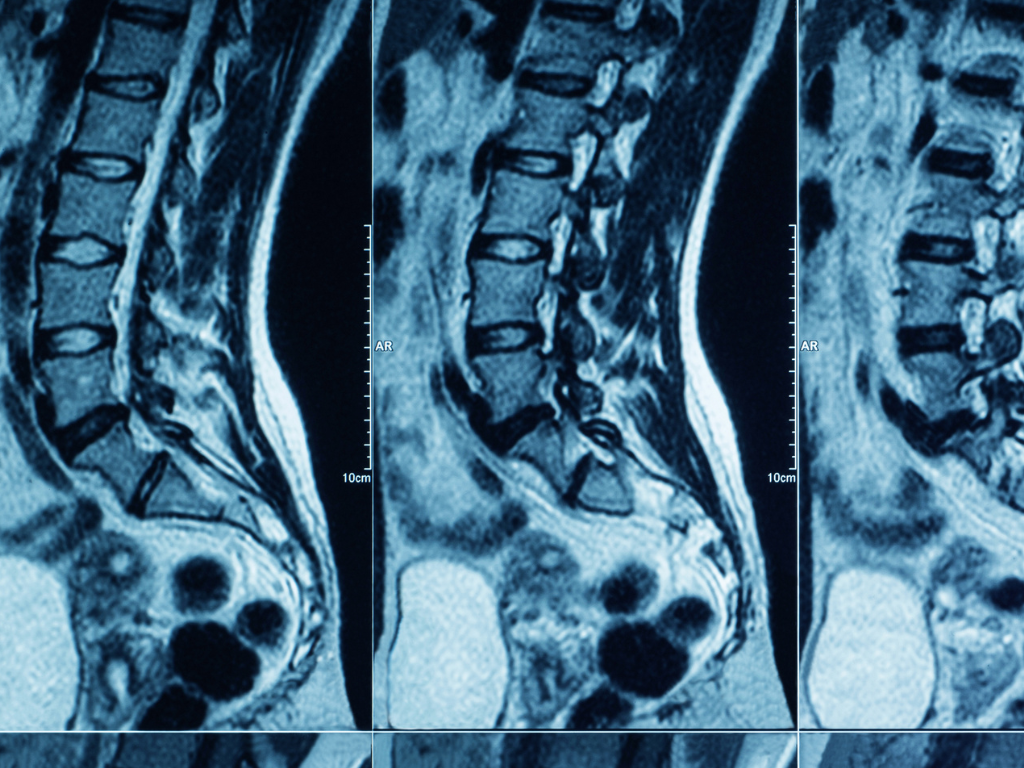

When the pain becomes severe or persistent, many people turn to doctors for help and are often sent for diagnostic imaging such as X-rays or MRI scans. The thinking is: If we can see what’s inside, we’ll know exactly what’s wrong.

Even more surprising is that many people without back pain at all have “abnormal” findings on an MRI. For example:

- Disc bulges are present in more than 50% (up to 90%) of people over age 60.

- Arthritic changes in the facet joints are common as part of normal aging.

- Degenerative disc disease often appears on imaging even when there are no symptoms.

In other words, seeing a disc bulge or arthritis on an MRI does not automatically mean that’s the cause of your pain.

This mismatch between imaging results and actual symptoms is well documented. Many people live pain-free despite having significant changes in their spine, while others experience intense pain with “normal” scans.